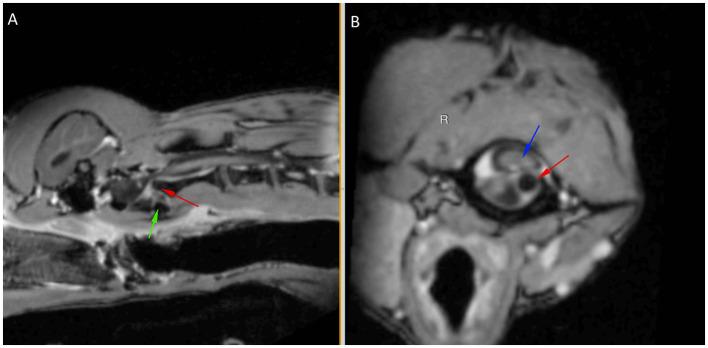

Ehlers-Danlos syndrome is a rare, heritable connective tissue disorder characterized by soft, hyperextensible skin, joint hypermobility, and tissue fragility, the severity of which can range from mild to severe. A 9-month-old male entire miniature Dachshund was presented following peracute tetraparesis. Neurological examination was suggestive of intracranial vestibular disease or high cervical myelopathy. MRI revealed atlantoaxial instability and subluxation, resulting in marked spinal cord compression at C1-C2, which was surgically stabilized. On discharge from the hospital, skin fragility was noted as the result of skin tearing during tape removal. A piece of full-thickness antebrachial skin was submitted for histopathology which showed changes consistent with Ehlers-Danlos syndrome. This case report describes the first case of atlantoaxial instability and subluxation in a dog as the result of a confirmed underlying collagenopathy.

埃勒斯-当洛综合征是一种罕见的遗传性结缔组织疾病,其特征为皮肤柔软、过度伸展,关节活动过度,以及组织脆弱,其严重程度可从轻度到重度。一只9个月大的雄性纯种迷你腊肠犬因急性四肢轻瘫前来就诊。神经学检查提示颅内前庭疾病或高位颈髓病。磁共振成像显示寰枢椎不稳和半脱位,导致C1-C2水平脊髓明显受压,遂进行手术固定。出院时,发现因去除胶带时皮肤撕裂而出现皮肤脆弱。取一块全层前臂皮肤进行组织病理学检查,结果显示与埃勒斯-当洛综合征相符的变化。本病例报告描述了首例因确诊潜在的胶原病导致犬寰枢椎不稳和半脱位的病例。